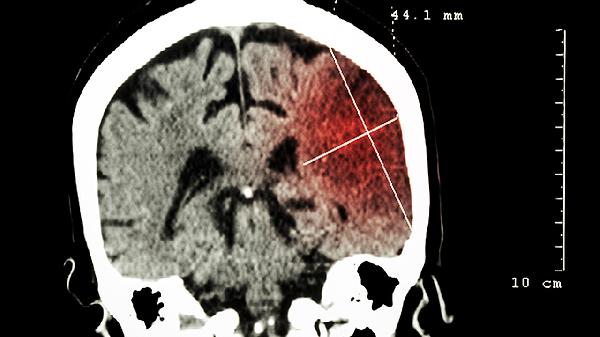

作为首选治疗方式,最大范围安全切除肿瘤可缓解占位效应。对于位于功能区的肿瘤,术中神经导航和唤醒麻醉技术能降低神经功能损伤风险。但胶质瘤浸润性生长的特性使完全切除困难,术后影像学检查常显示残余病灶。

术后6周内开始常规放疗,采用调强放疗技术精准照射肿瘤床及周边2cm区域。对于复发病例可选择立体定向放射外科治疗。放疗可破坏肿瘤细胞DNA,延缓复发时间约6-12个月,但可能引起放射性脑坏死等并发症。